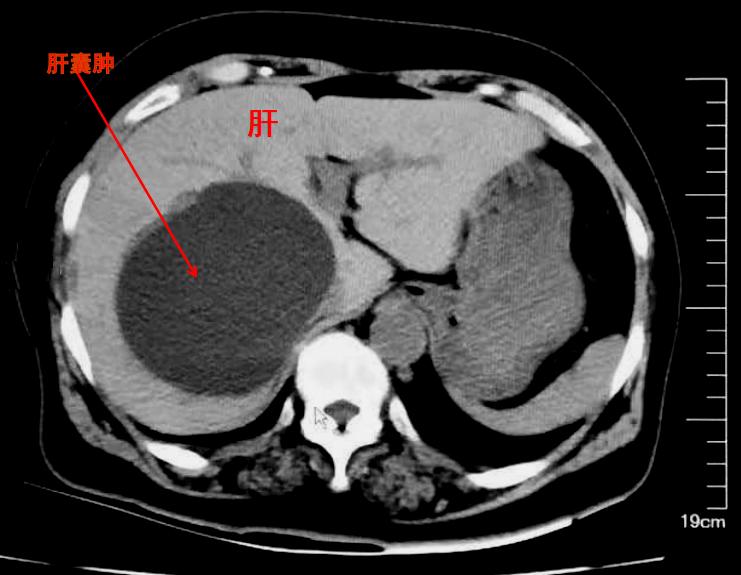

肝囊肿,并不是肿瘤

举一些实例来看:囊肿、血肿、肉芽组织增殖等,都不是肿瘤,但却通常表现为肿块,在前面的病例中,小李的腕部所摸到的腱鞘囊肿,就表现为肿块,但却并不是肿瘤(有时也被称为肿瘤样病变)。

与前图相似,但却是真肿瘤(囊腺瘤)